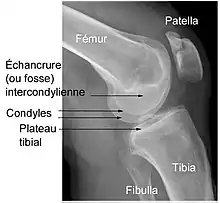

Éléments d'anatomie du genou

Le genou naturel est composé de trois parties osseuses :

- l’extrémité inférieure du fémur qui a la forme de deux roues accolées : les condyles ;

- l’extrémité supérieure du tibia, encore appelé plateau tibial ;

- la patella (ou rotule) : petit bouclier situé sur l’avant du fémur.

À ceci s'ajoutent d'autres éléments, favorisant le fonctionnement parfois très contraignant de l'articulation (voir schéma) :

- Une couche de cartilage recouvrant chaque partie osseuse en regard d'une autre : condyles fémoraux, partie antérieure du fémur, face postérieure de la patella et plateau tibial.

- Deux petits coussins de cartilage fibreux, les ménisques, disposés entre le fémur et le tibia. En forme de croissant mobile — seules les cornes s'insèrent sur le plateau tibial —, ils augmentent la congruence articulaire et amortissent le contact entre le cartilage du fémur et celui du tibia. Ils sont situés l'un vers l’intérieur (ménisque médial ou interne, qui répond au condyle médial du fémur) et l'autre vers l’extérieur du genou (ménisque latéral ou externe, en regard du condyle latéral).

- Des ligaments assurant la stabilité de l’articulation, et dont les principaux sont :

- deux ligaments croisés :

- le ligament croisé antérieur (LCA) — ligament croisé antéro-externe (LCAE), dans l'ancienne nomenclature —, son origine se trouve sur la surface pré-spinale de l'espace intercondylaire du plateau tibial, entre les cornes méniscales. Il se dirige en haut, en arrière et en dehors pour venir s'insérer sur la surface intercondylienne du condyle fémoral latéral. Le LCA croise en dehors le :

- ligament croisé postérieur (LCP) — ou ligament croisé postéro-interne (LCPI) de l'ancienne nomenclature —, de son origine, sur la surface rétrospinale de l'aire intercondylaire, il se dirige en haut, un peu en avant et en dedans, pour s'insérer sur la surface intercondylienne du condyle fémoral médial.

- Deux ligaments collatéraux : ligament collatéral tibial (ou interne) et ligament collatéral fibulaire (ou externe) maintenant le genou en dedans et en dehors. Les ligaments collatéraux sont également croisés, permettant une bonne stabilité du genou.

- Les ligaments maintenant la patella : le tendon patellaire (rotulien), reliant la patella au tibia et les tendons du muscle quadriceps reliant la patella à la cuisse. Ils assurent la transmission de la traction du quadriceps sur le tibia même en position de forte flexion du genou, la patella agissant comme poulie.